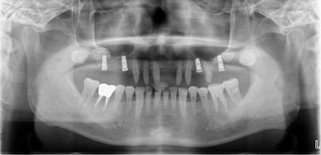

昨日は右下奥歯にインプラント埋入をおこない、上顎は去年、両方の奥歯を同日にサイナスリフトをおこない、同時にインプラント埋入をおこないました。

上顎両側同時にサイナスリフトをおこない、同時にインプラント埋入をおこないました。